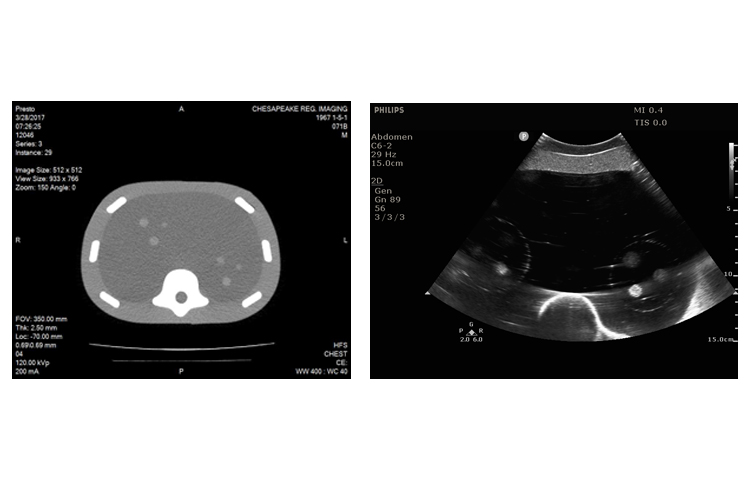

美國(guó)CIRS 071B腹部穿刺模體

CIRS 071B圖像引導(dǎo)腹部穿刺模體是一種簡(jiǎn)化的腹部模型,適用于訓(xùn)練和演示圖像引導(dǎo)的穿刺活檢導(dǎo)航工具或程序,需要持續(xù)的視覺(jué)參考針頭放置。因?yàn)樗怯蒢erdine的自我修復(fù)配方構(gòu)成,所以體模允許多次活組織檢查插入,最小的針跟蹤。

CIRS 071B圖像引導(dǎo)腹部穿刺模體包含12個(gè)病灶,直徑5-12mm,以三個(gè)一組的方式放置在體模內(nèi)的一致位置。它還包括模擬脊柱和肋骨,以及脊柱內(nèi)的“H”標(biāo)記,以幫助確定CT圖像中的頭側(cè)。

在超聲,CT和MRI下可見(jiàn)病變和脊柱。固體聚合物凝膠背景是消聲的,穿刺時(shí)不會(huì)泄漏。